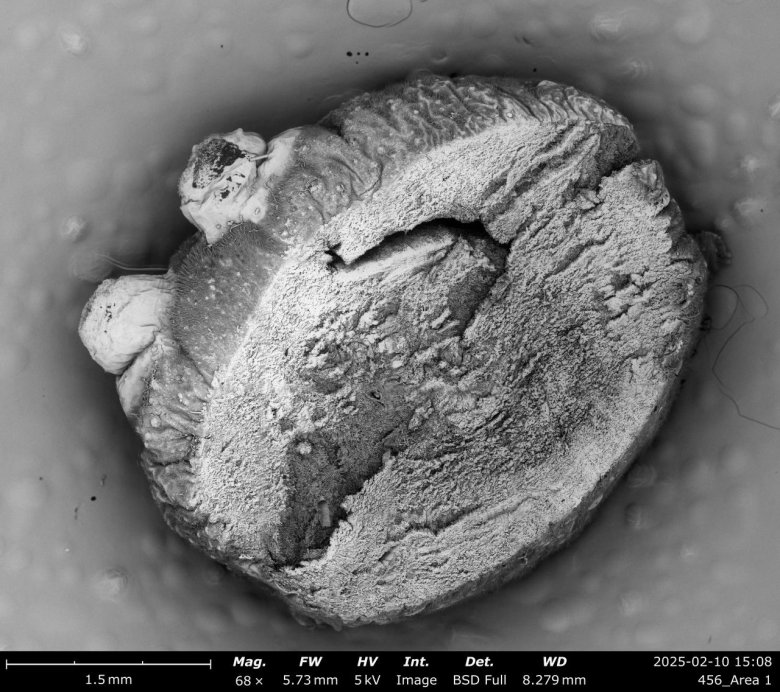

冬蟲夏草的微觀探索

冬蟲夏草作為藏藥中的瑰寶,具有極高的藥用價值。研究表明,冬蟲夏草含有多種活性成分,如蟲草素、蟲草多糖和腺苷等,這些成分具有免疫調節、抗腫瘤、抗氧化等多種藥理作用。飛納電鏡的高分辨率成像能力將為研究人員提供更清晰的微觀結構信息,幫助他們深入理解冬蟲夏草的活性成分及其作用機制。

1使用飛納電鏡 Phenom XL 觀測冬蟲夏草,光學導航模式。

2使用飛納電鏡的 AIM 超清大視野全景拼圖,可以在電鏡模式下完整重現冬蟲夏草的整體形貌。